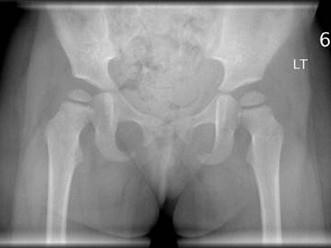

女,请根据其正常骨盆影像图像,判断其最可能的年龄 ( )A、11岁左右B、14岁左右C、5岁左右D、8岁左右E、2岁左右

问题 女,请根据其正常骨盆影像图像,判断其最可能的年龄 ( )

选项 A、11岁左右 B、14岁左右 C、5岁左右 D、8岁左右 E、2岁左右

答案 E